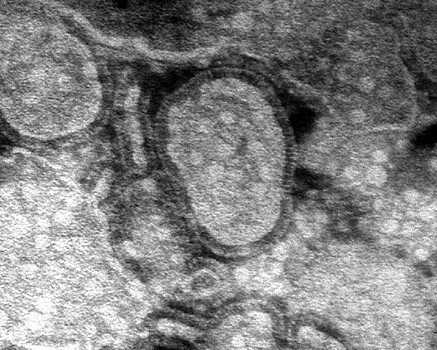

Вирусолог, ведущий научный сотрудник Института клинической и экспериментальной медицины Александр Чепурнов прокомментировал слухи о том, что в России сейчас распространяется «вирус-убийца» hMPV. Речь идёт о метапневмовирусе, который проявляется как ОРВИ.

По словам эксперта, на самом деле метапневмовирус не летален так, каким был коронавирус. Он отметил, что после пережитой пандемии любой вирус может вызвать панику, но «вирусом-убийцей» hMPV не является.

К тому же для медицины метапневмовирус не является чем-то неизвестным. Эта нозологическая форма изучается с 2000-х годов.

Сам по себе метапневмовирус ничего особого не представляет. Да, новая нозологическая форма, известная вот уже какое-то количество лет. Александр Чепурнов Вирусолог, ведущий научный сотрудник Института клинической и экспериментальной медицины